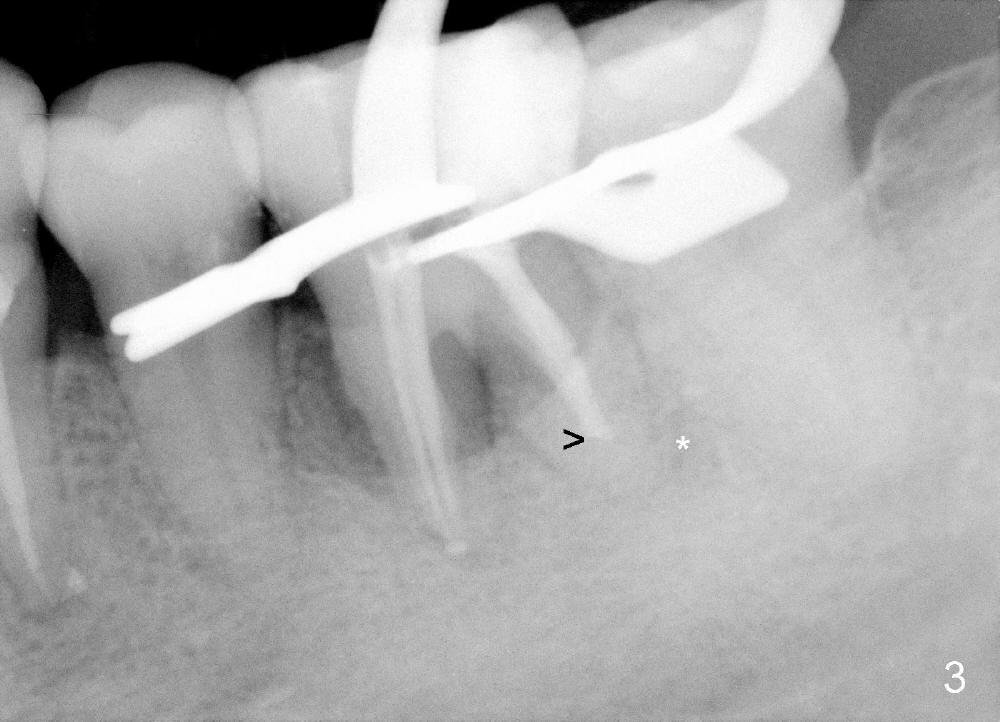

Considering severe bone resorption, a 6.9x10 mm bone-level (Fig.4) or 7x14 mm gingiva-level (Fig.5) implant does not seem to be long enough to achieve primary stability. Probably a 7x17 mm gingiva-level implant is more appropriate, but it carries more risk of nerve injury. Be careful. Take several intraop PAs for depth confirmation. Try shorter osteotomy and implant first and use longer one if necessary.